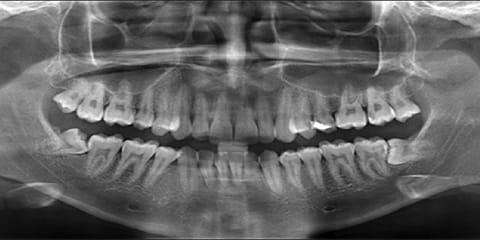

OPG and RVG are digital dental X-rays that give clear and detailed images of your teeth and jaw. They help in accurate diagnosis and allow the dentist to plan safe and effective treatment.

OPG and RVG